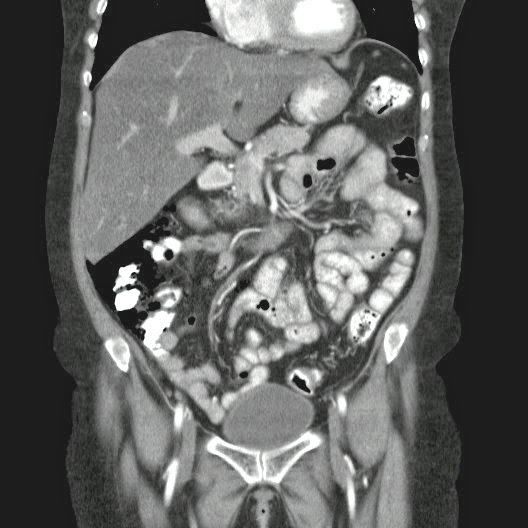

Paciente con antecedente de ALIF (Fusión lumbar intersomática anterior) 360 grados L5-S1 hace siete meses, quién presenta herida de abordaje anterior con dehiscencia de sutura, con cierre por segunda intención, quien consulta por cuadro clínico de dos días de secreción purulenta en herida quirúrgica, niega fiebre, niega otras sintomatología, refiere episodios previos similares.

Paciente en POP de ALIF L5-S1 quien presento dehiscencia de la herida abdominal con ISO superficial ya tratada, sin embargo persiste con dehiscencia y desde ayer con supuración asociado a fiebre subjetiva. Se realiza eco abdominal con colección en pared sugestiva de absceso, elevación de RFA por lo cual se considera se debe hospitalizar para manejo antibiótico, drenaje de la colección, manejo médico y vigilancia neurológica.

- ¿Hallazgos Escanografia?

2. Hay una colección de la pared abdominal en el flanco derecho, que realza en la periferia con el contraste, e intraabdominal tiene aire pero no me parece colección intraabdominal porque la grasa no está alterada.